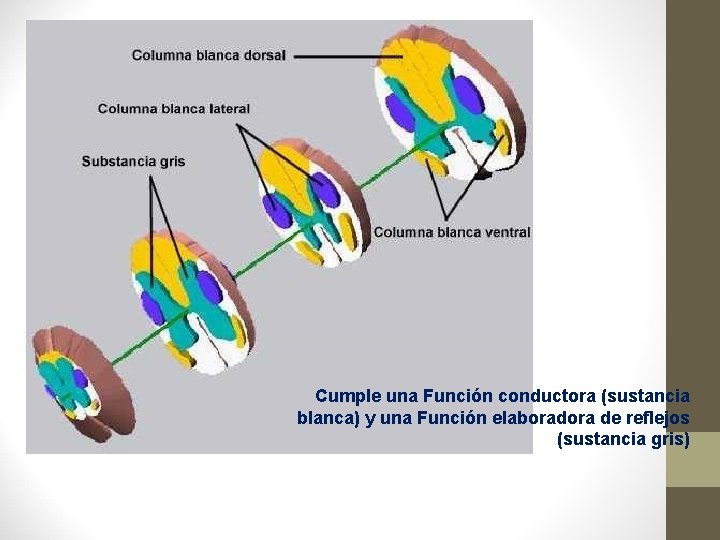

Cumple una Función conductora (sustancia blanca) y una Función elaboradora de reflejos (sustancia gris)